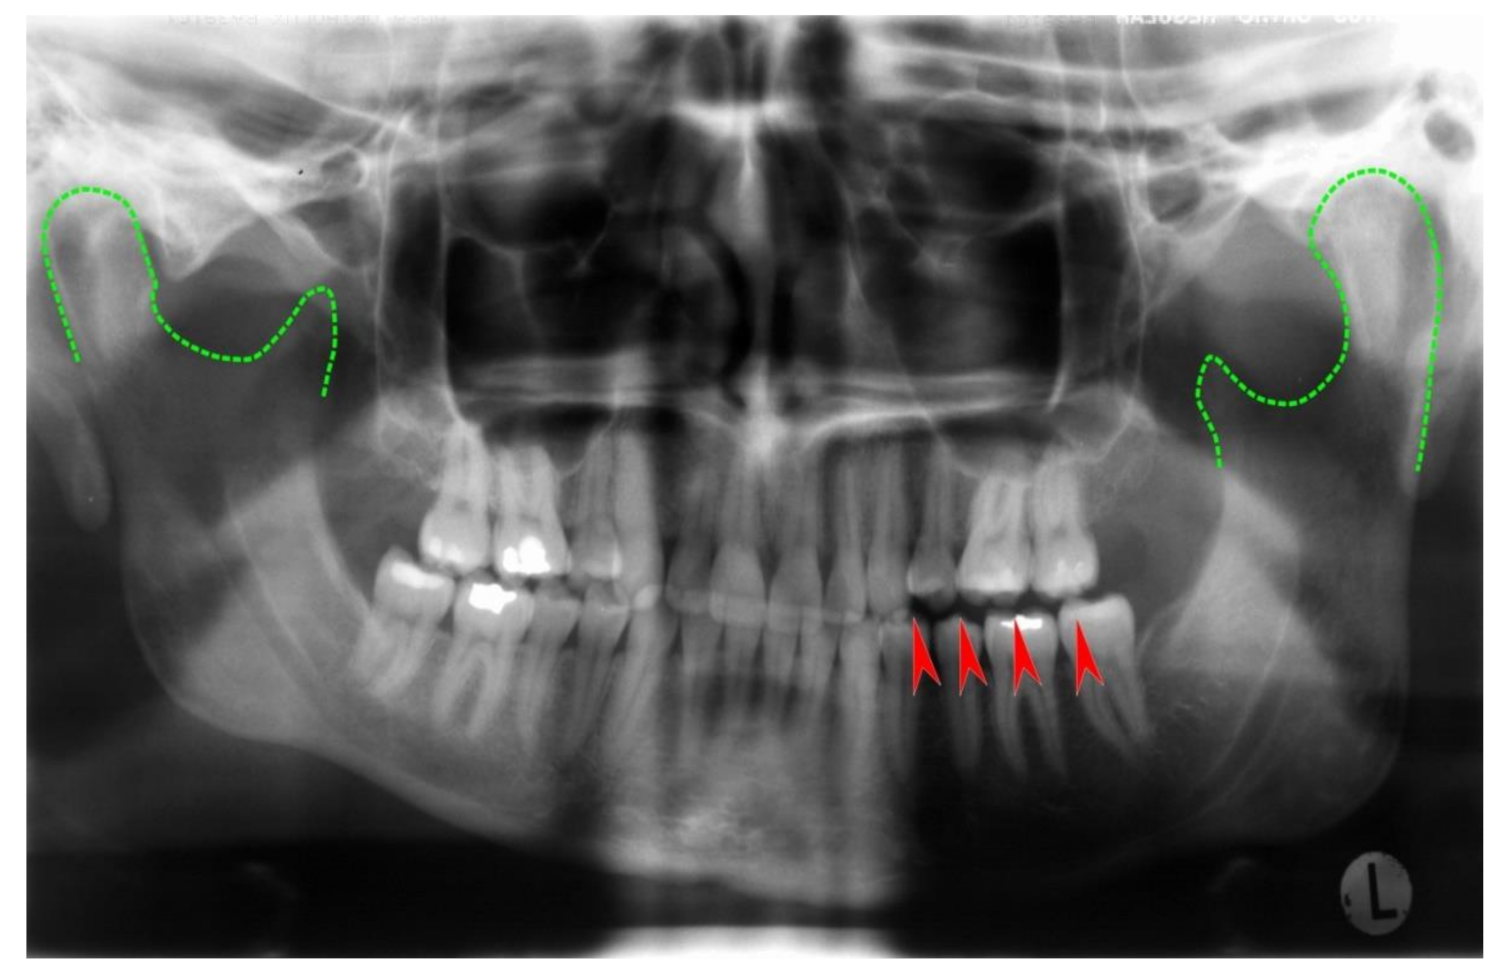

Unilateral mandibular condylar hyperplasia is a rare disease, where one condyle exhibits excessive growth [124,125,126]. A benign tumor of the long bones, osteochondroma, may also affect the mandibular condyle with similar consequences: Condylar growth leads to dislocation of the mandibular body in vertical and/or anterior direction. Asymmetry and occlusal imbalances are frequent consequences (Figure 10 and Figure 11). Treatment includes surgical remodeling or removal of the affected condyle and, if necessary, insertion of a neocondyle.

Figure 10.

Panoramic radiograph of a unilateral condylar hyperplasia on a 38-year-old female patient’s left side. Green dotted lines outline the condyles; arrows indicate non-occlusion in the left bicuspid and molar region. In this case, the panoramic radiograph gives an impression of asymmetry. However, CT and cone beam CT are superior in accuracy.